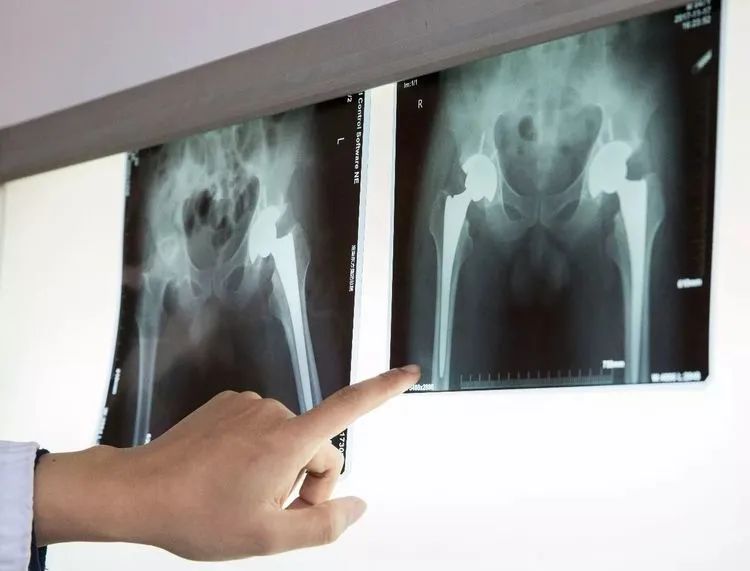

家住寿县的马大娘,十五年前开始出现双侧髋关节疼痛,随着时间的推移,疼痛越来越厉害,腿不能屈,蹲也蹲不下。经人推荐,马大娘一家来到了淮南东方医院集团广济医院骨科就诊。完善检查后,明确诊断为“双侧先天性髋关节发育不良(DDH)、双侧股骨头无菌性坏死”,骨科王怀波主任邀请广济骨科首席专家方成教授共同开展术前讨论,迅速为其拟定“右侧全髋关节置换术”。

方成教授介绍说,近年来,国内髋关节疾病的发病率迅速增长,每年近100例人工关节置换术中,髋关节置换术比例接近一半,每年以20%的速度在增长。如果把人体骨骼系统比作汽车,髋关节就是其中最重要的轴承。髋关节出现问题,会产生难以忍受的疼痛,影响人们正常的活动,而活动的减少不仅容易带来情感上的抑郁,还会导致生活质量严重下降,随之导致各个器官系统机能下降,衰老加速。